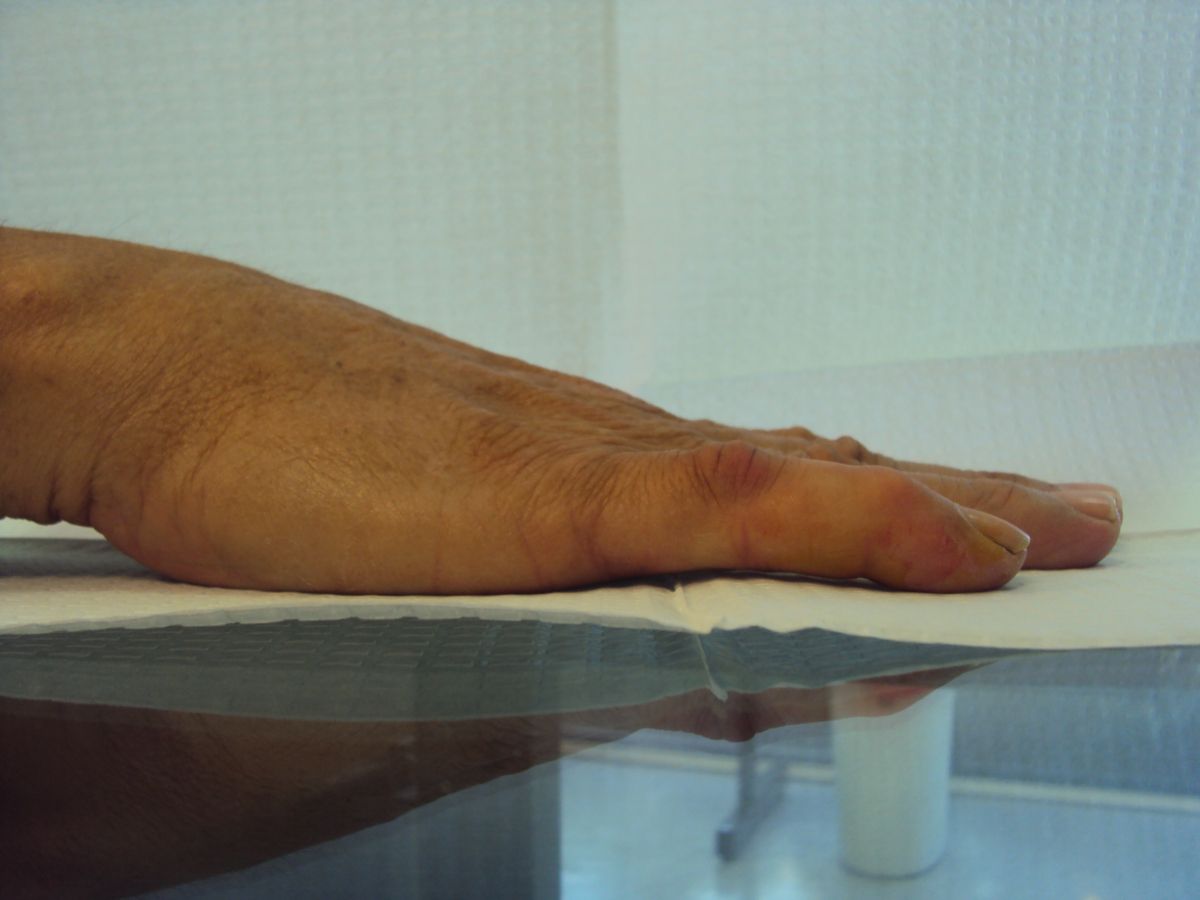

Case 1.

40 year old right handed man with several year history of

minimal bilateral Dupuytren disease. The left small finger

has reached a point of functional impairment from combined

proximal and distal interphalangeal joint contractures.